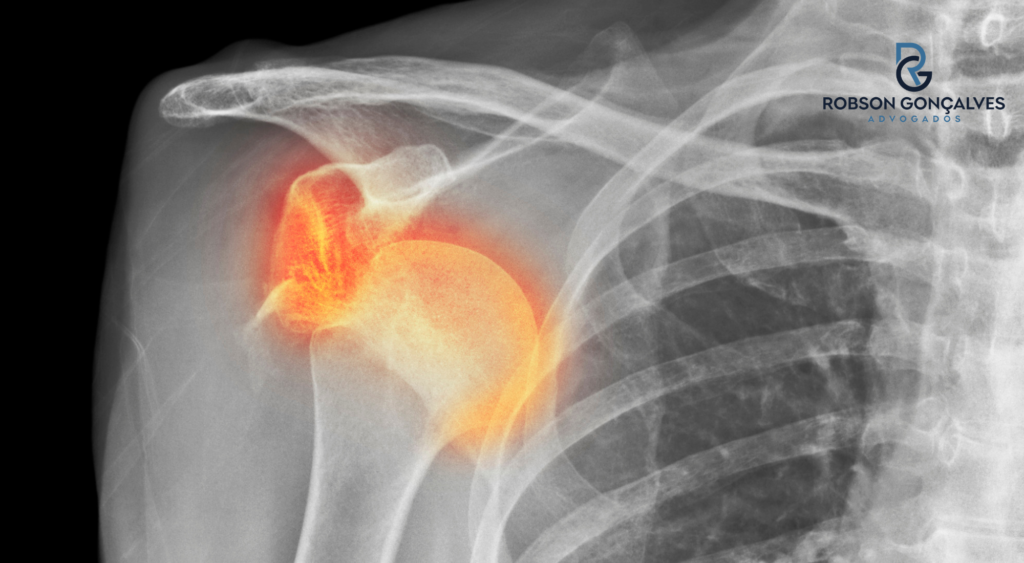

A luxação acromioclavicular é uma lesão na articulação entre a clavícula e o acrômio, que faz parte da escápula.

Em termos simples, é um “desencaixe” da junção entre a clavícula e o ombro.

No CID 10, essa lesão costuma aparecer como S43.1 ou S431, que é o código específico para luxação da articulação acromioclavicular.